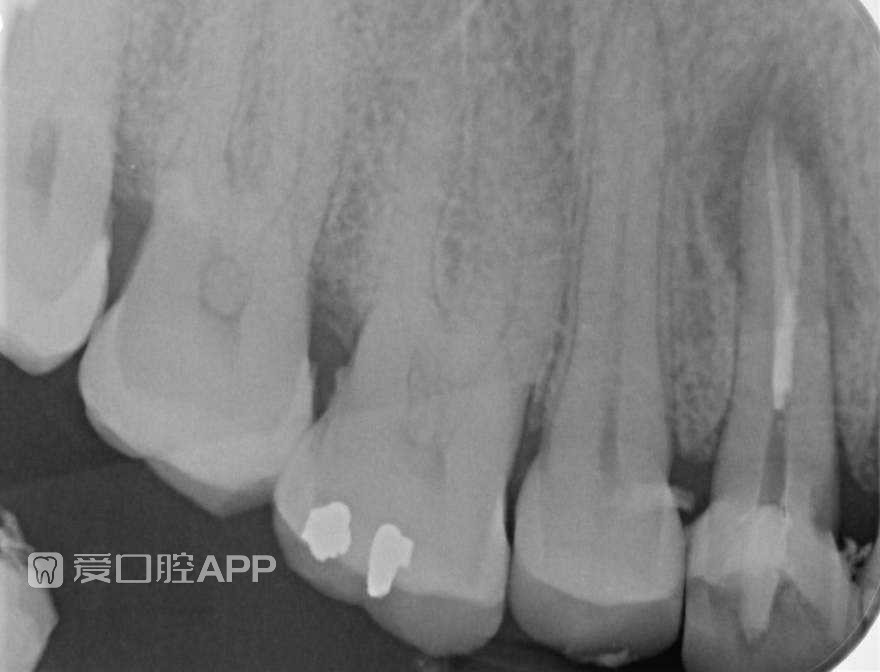

上颌第一前磨牙根管治疗1例

By Jorge Zapata